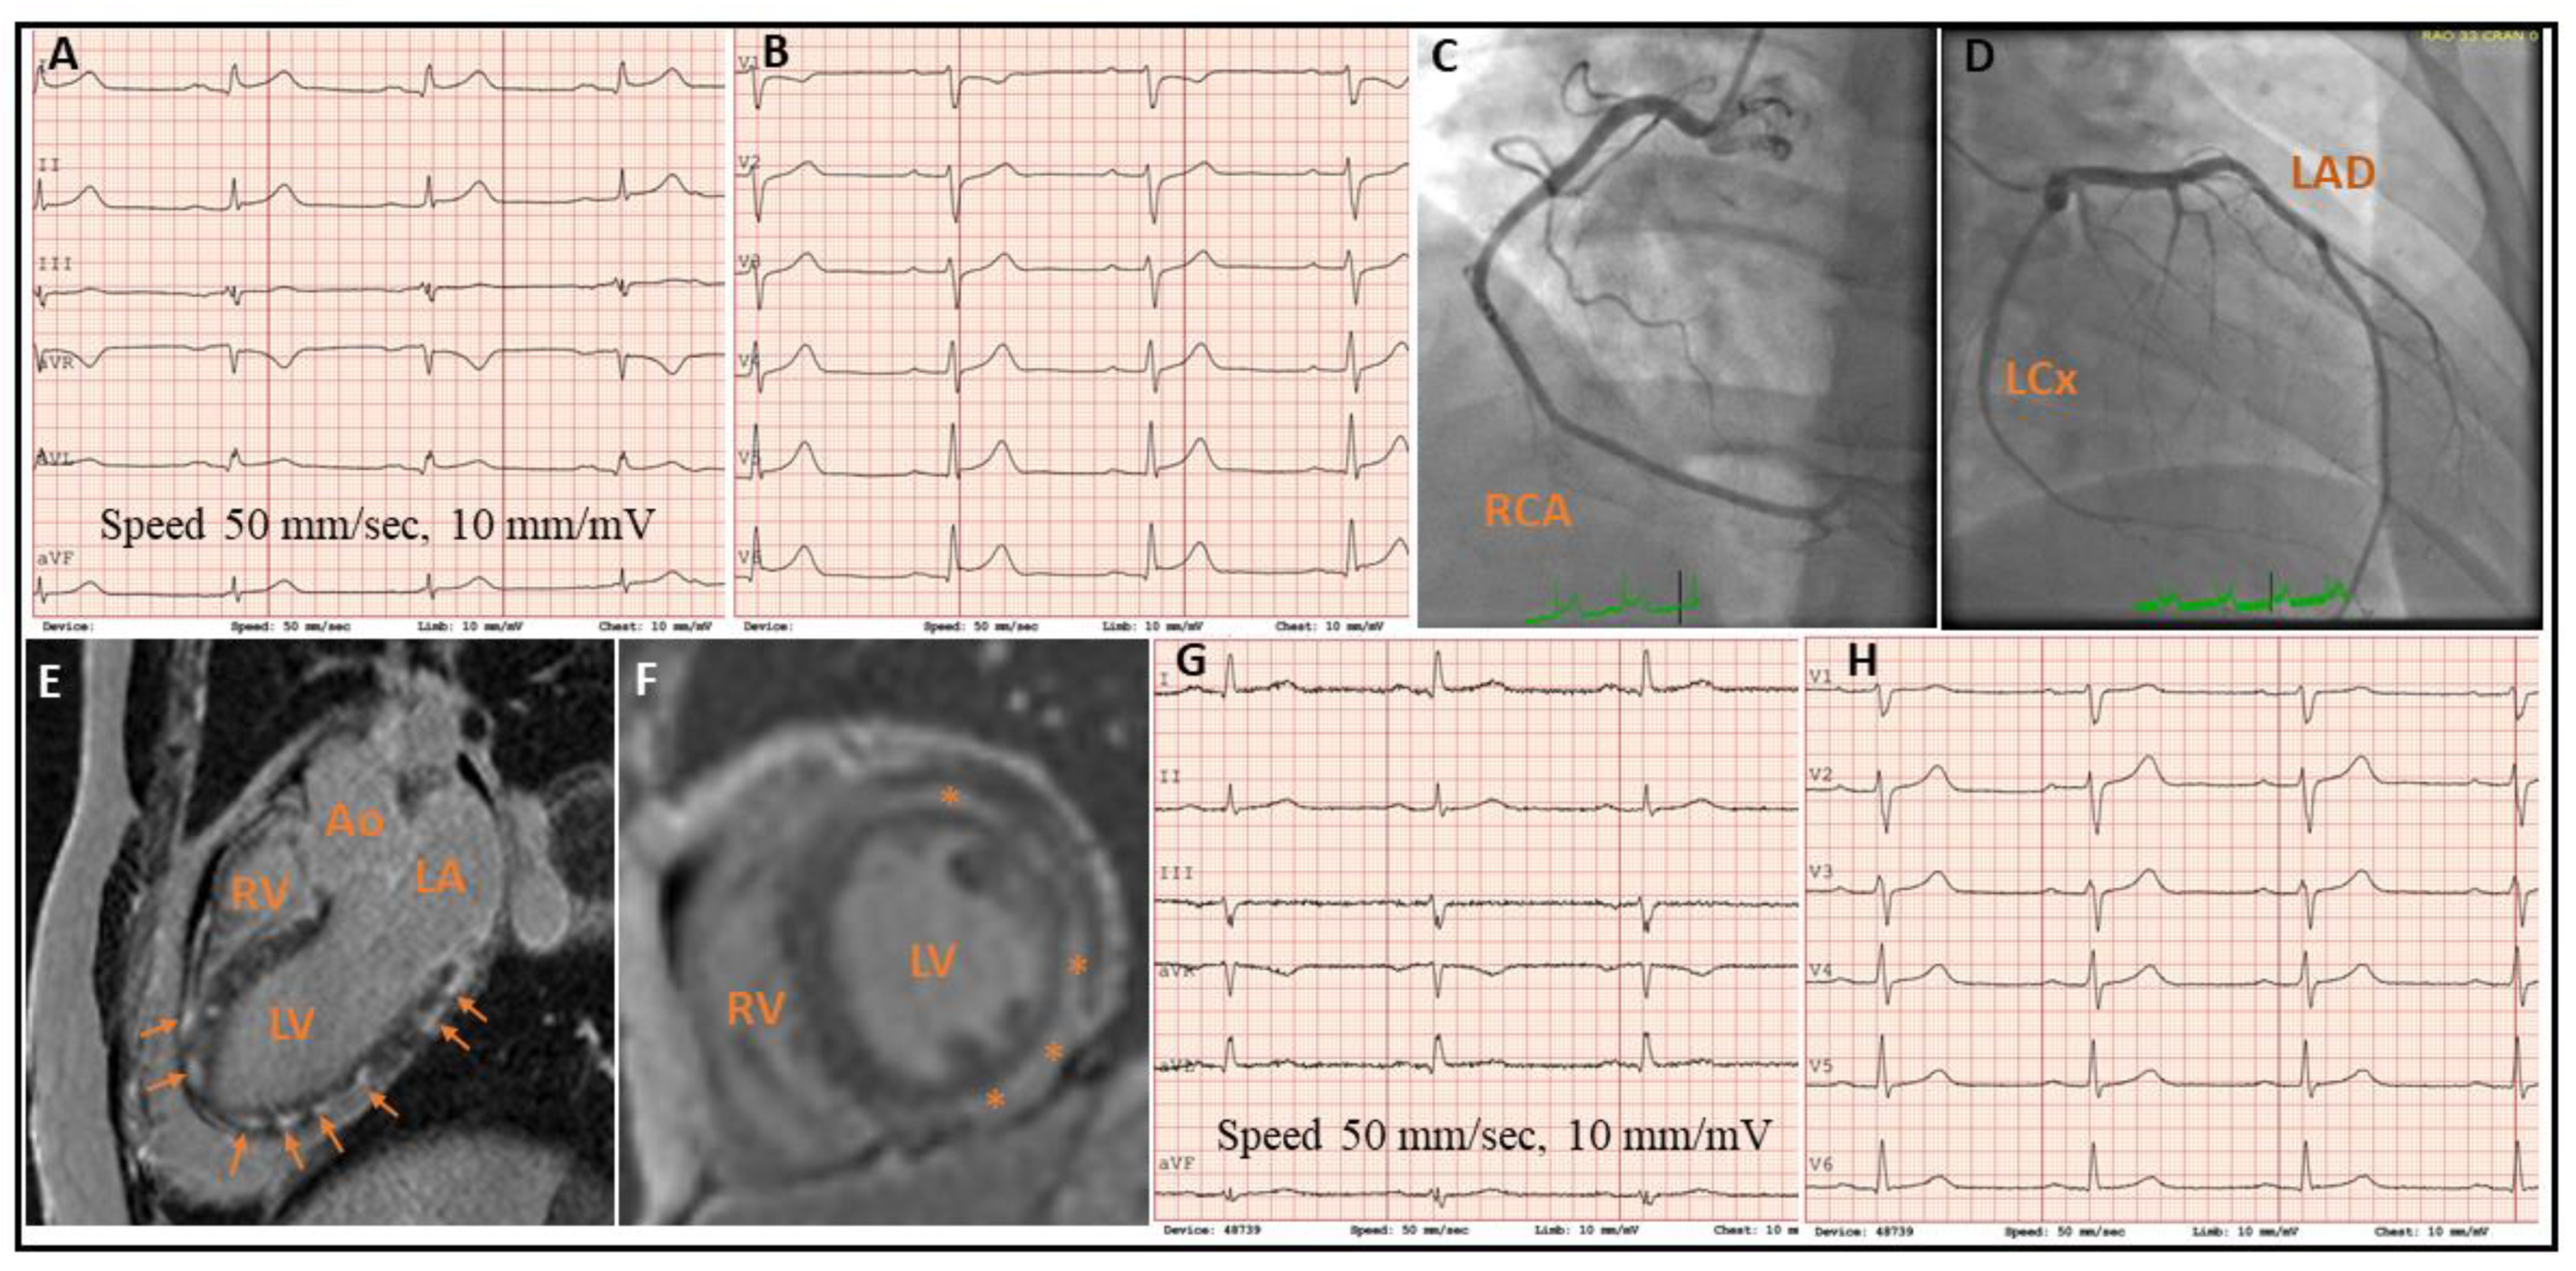

2. Case Presentation